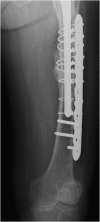

We report an 85-year-old patient with severe osteoporosis who had suffered from multiple episodes of periprosthetic fracture of the femur. Revision fixation with long-spanning cable plate for bisphosphonate-induced atypical periprosthetic femoral fracture was performed. Nonunion and implant failure occurred at 16 months requiring revision surgery using long-stem femoral prosthesis with cable-plate fixation. To further facilitate bone healing, allograft and bone morphogenetic protein (BMP) were added. Eventually bone union was achieved after one year.